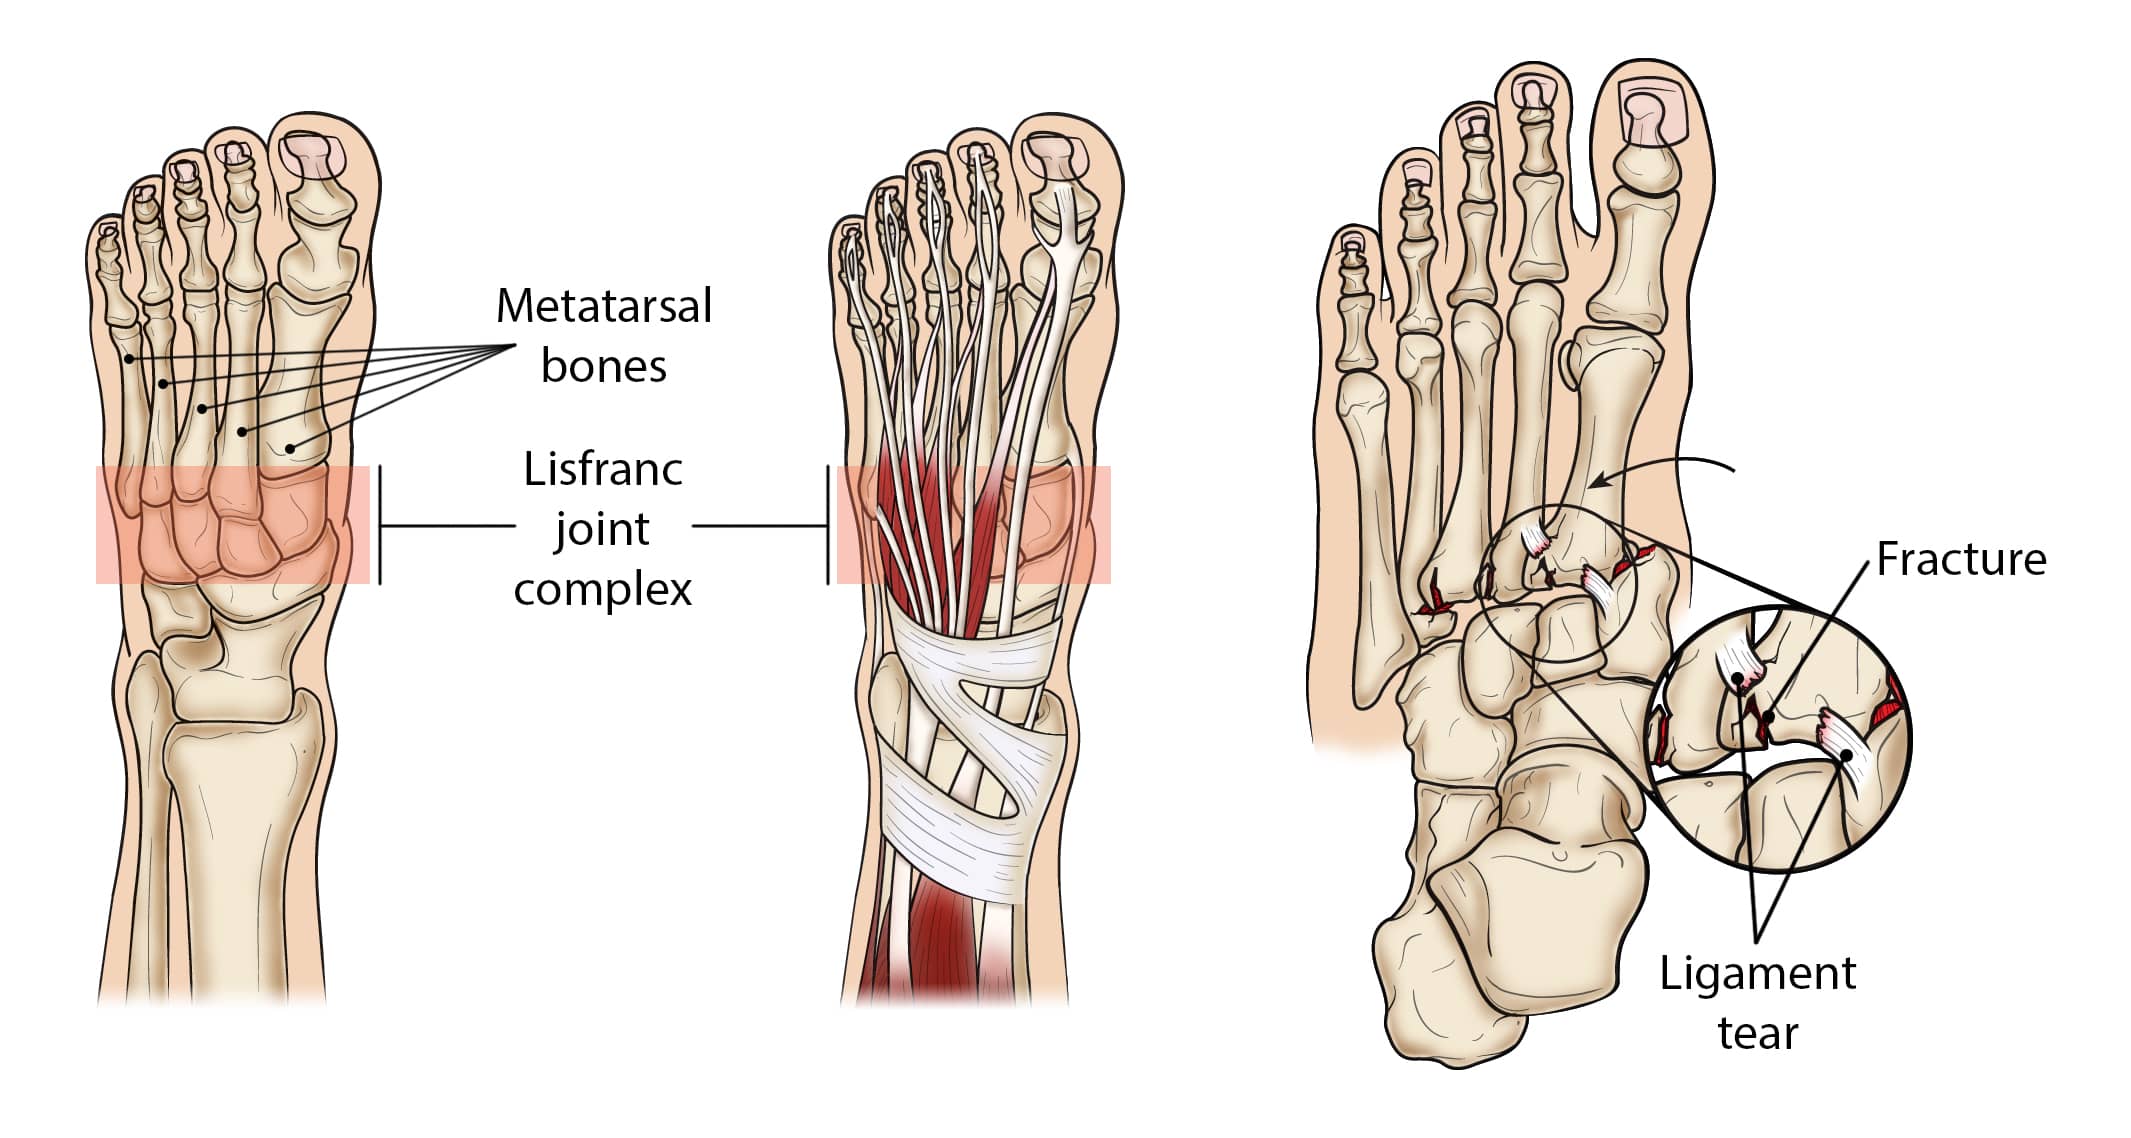

The midfoot is the middle region of the foot, where a cluster of small bones forms the arch on the top of the foot. From this cluster, five long bones (metatarsals) extend to the toes.

The bones are held in place by strong ligaments, known as the Lisfranc joint complex, that stretch both across and down the foot. However, there is no connective tissue holding the first metatarsal to the second metatarsal. A twisting fall can break or shift (dislocate) these bones out of place.

Lisfranc joint complex

The Lisfranc joint complex includes the bones and ligaments that connect the midfoot and forefoot. Lisfranc injuries include ligament strains and tears, as well as fractures and dislocations of bone (far right).